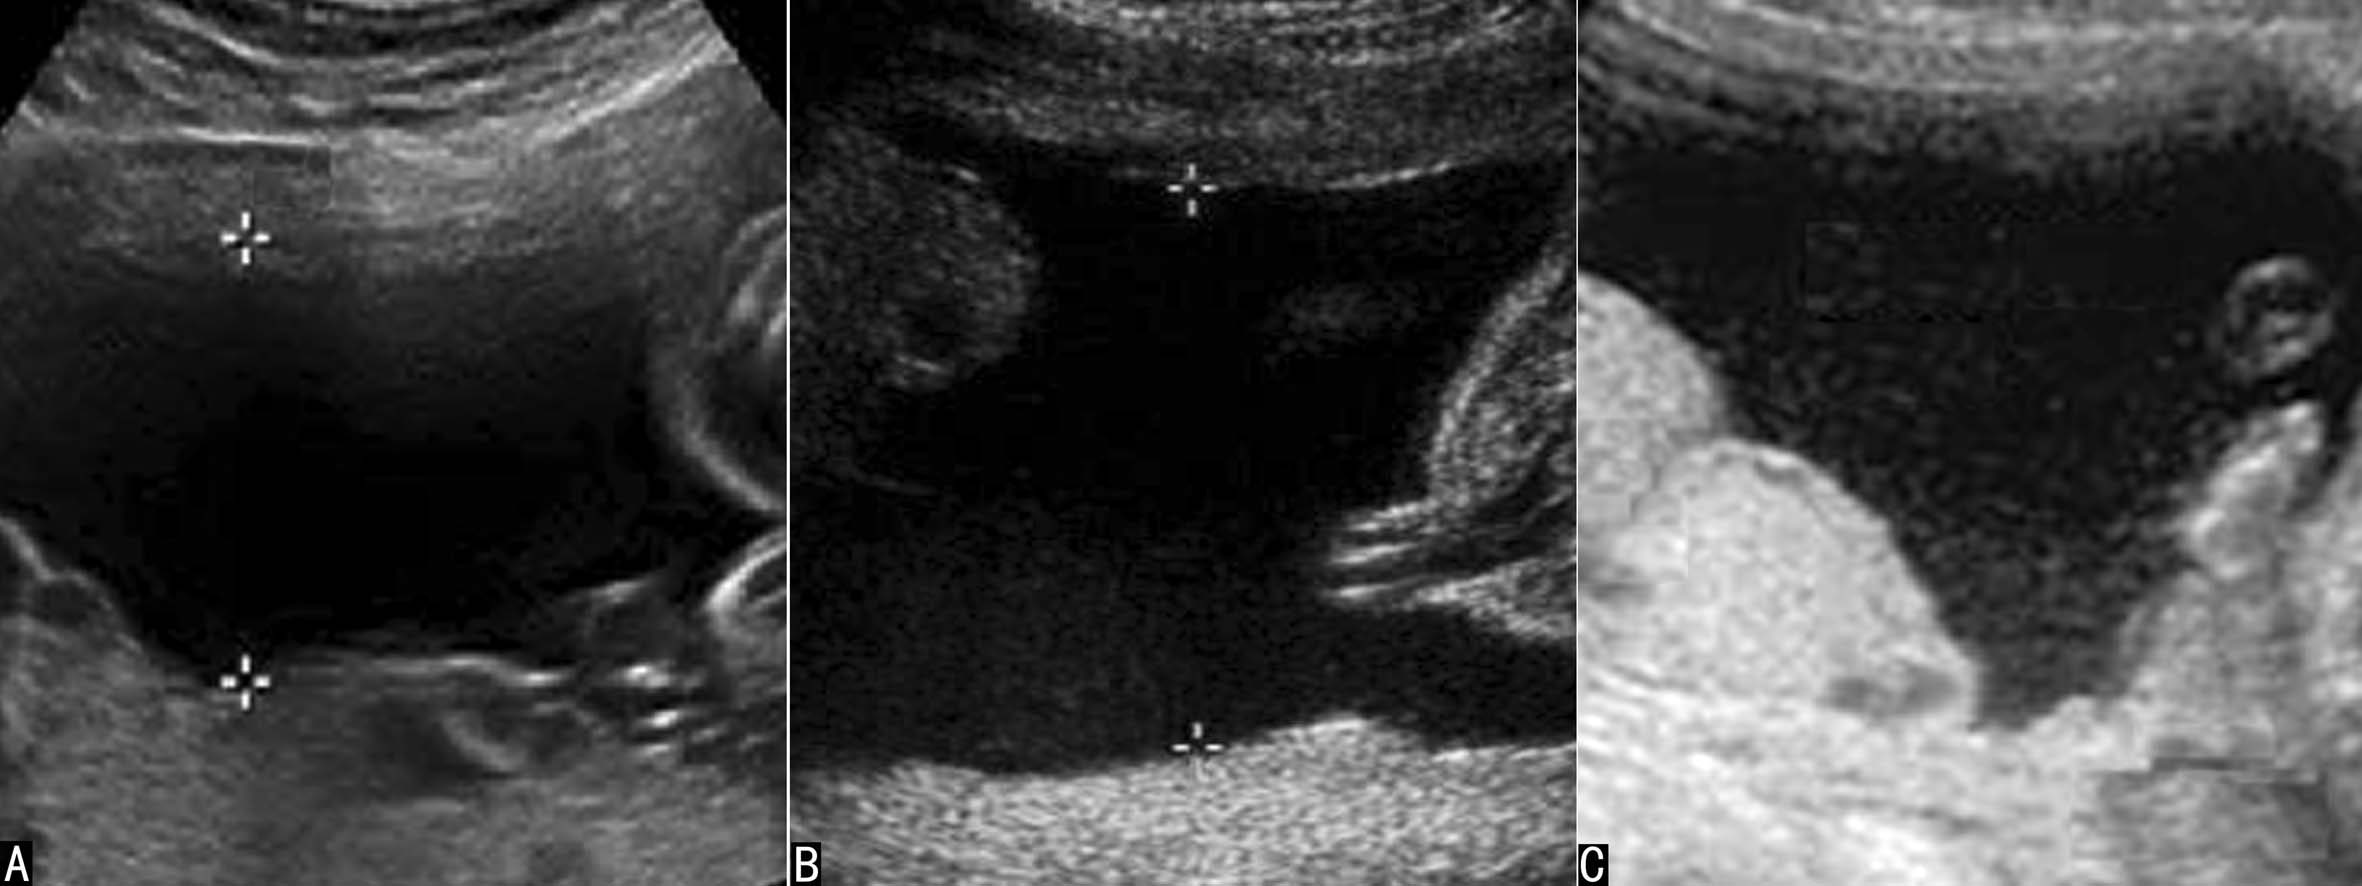

图2中晚期妊娠羊水显示

晚期妊娠过程中羊水声像图的变化较快,主要表现在羊水回声性质的改变和羊水量的减少,应当注意适时检查并作出相应的评价。晚期妊娠时羊水内部的点状回声逐渐增多,在胎儿活动时可以发现少许漂起的点状回声,停止活动后回声点可以缓慢下落;越临近分娩,羊水内部的点状回声越多(见图2C)。这些漂浮的回声可能与胎儿皮肤脱离的皮脂有关。过期妊娠或胎儿宫内窘迫时常可在短期内发现羊水内点状回声明显增多,严重时羊水内可见弥漫分布的均匀、低水平的点状回声,脐带血管在其内显示为纯净的无回声区,同时伴有羊水量的减少。

妊娠早期的羊水在声像图上显示为纯净的无回声区,胚胎或胎儿及脐带在羊水无回声区内显示得非常清楚(图1),直至中期妊娠的后期超声显像检查羊水内有时可以显示少量较低的点状回声(图2)。